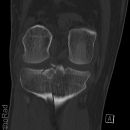

Intraossäres Hämangiom